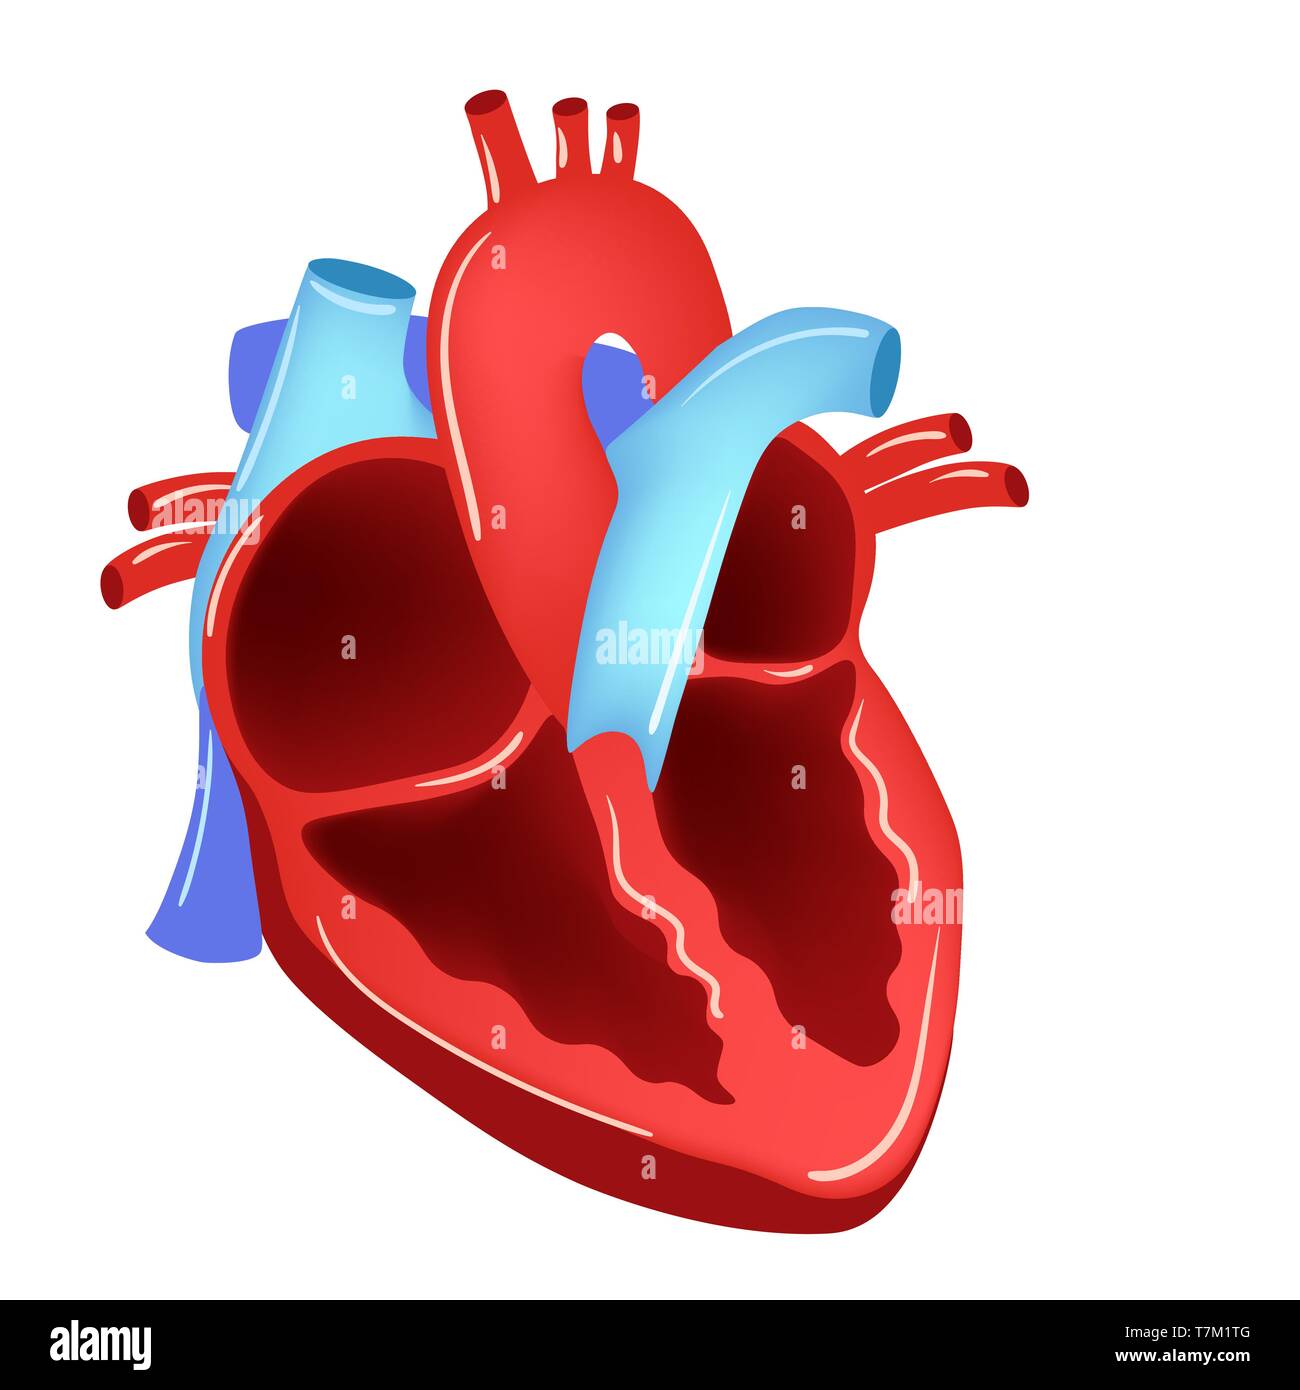

Vector illustration of Heart - Part of Human Organic. Stock Vectorhttps://www.alamy.com/image-license-details/?v=1https://www.alamy.com/vector-illustration-of-heart-part-of-human-organic-image245688237.html

Vector illustration of Heart - Part of Human Organic. Stock Vectorhttps://www.alamy.com/image-license-details/?v=1https://www.alamy.com/vector-illustration-of-heart-part-of-human-organic-image245688237.htmlRFT7M1RW–Vector illustration of Heart - Part of Human Organic.